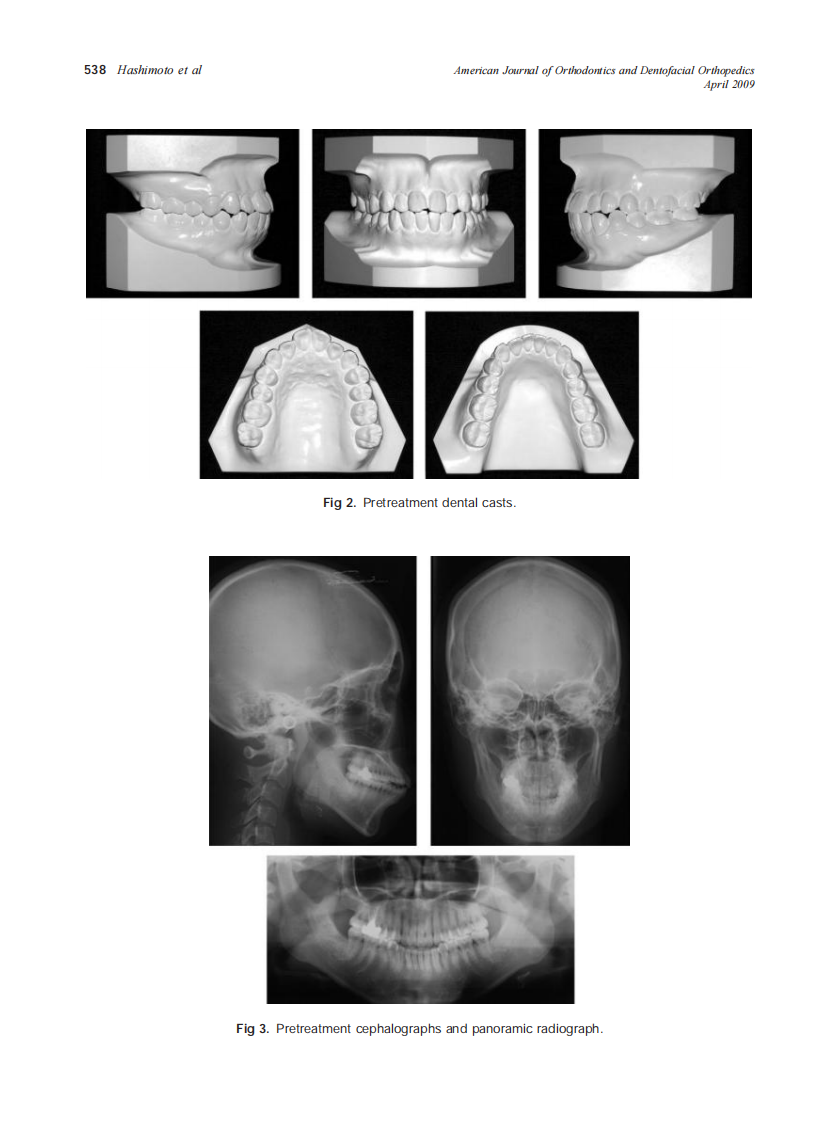

2009_135_4_536_548_Hashimoto.pdf